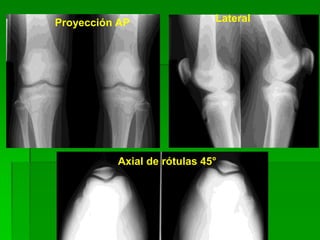

Rodilla frente (AP)

 Posición del paciente: Decúbito dorsal o

sentado sobre la mesa, la pierna extendida

sobre el chasis y rotación interna del pie.

 Rayo director: Puede incidir en forma

perpendicular sobre el vértice inferior de la

rotula o con angulación cefálica de 5 a 7

grados.

PROYECCION AP DE RODILLA

 EL PACIENTE se coloca en posición supina, con

la pierna completamente extendida.

 LA PELICULA 18 x 24. 24 x 30

 EL CHASIS: longitudinal.

 Colocar protección gonadal.

 EL RAYO: es perpendicular al plano, dirigido a

un punto medio de la rotula.(también 5º cefálico).

 ESTRUCTURAS MOSTRADAS: extremo distal

del fémur, el extremo proximal de la tibia y el

peroné. El espacio articular femorotibial, y las

carillas articulares de la tibia se observan en sus

extremos con una minima parte de su superficie.

Proyección AP Lateral

Axial de rótulas 45°